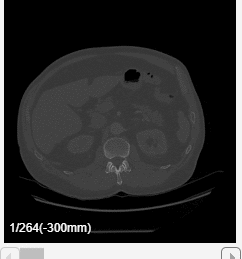

The app displays volumes as 2-D slice planes and a 3-D volume in a four-pane view. The 2-D slices are displayed in the Transverse, Sagittal, and Coronal planes. If your volume has incomplete or oblique spatial metadata, the app displays the volume without anatomical labels.

View 2-D Slices

To explore the volume, zoom in on a slice pane using the scroll wheel or the zoom controls in the top-right corner of the slice. Navigate between slices by using the scroll bar in each of the 2-D slice panes. The app also displays anatomical display markers indicating the anterior (A), posterior (P), left (L), right (R), superior (S), and inferior (I) directions. Labels in the bottom-left corner of each slice pane indicate the slice position in world coordinates, the current slice number, and the total number of slices in that dimension. When you display multiple volumes or labels as an overlay, the app hides the slice numbers and shows only the position values. The bottom of the app window displays information about the pixel beneath the pointer, including its coordinates and intensity. Note that, if you import a volume with limited spatial metadata, the app hides the anatomical display markers.